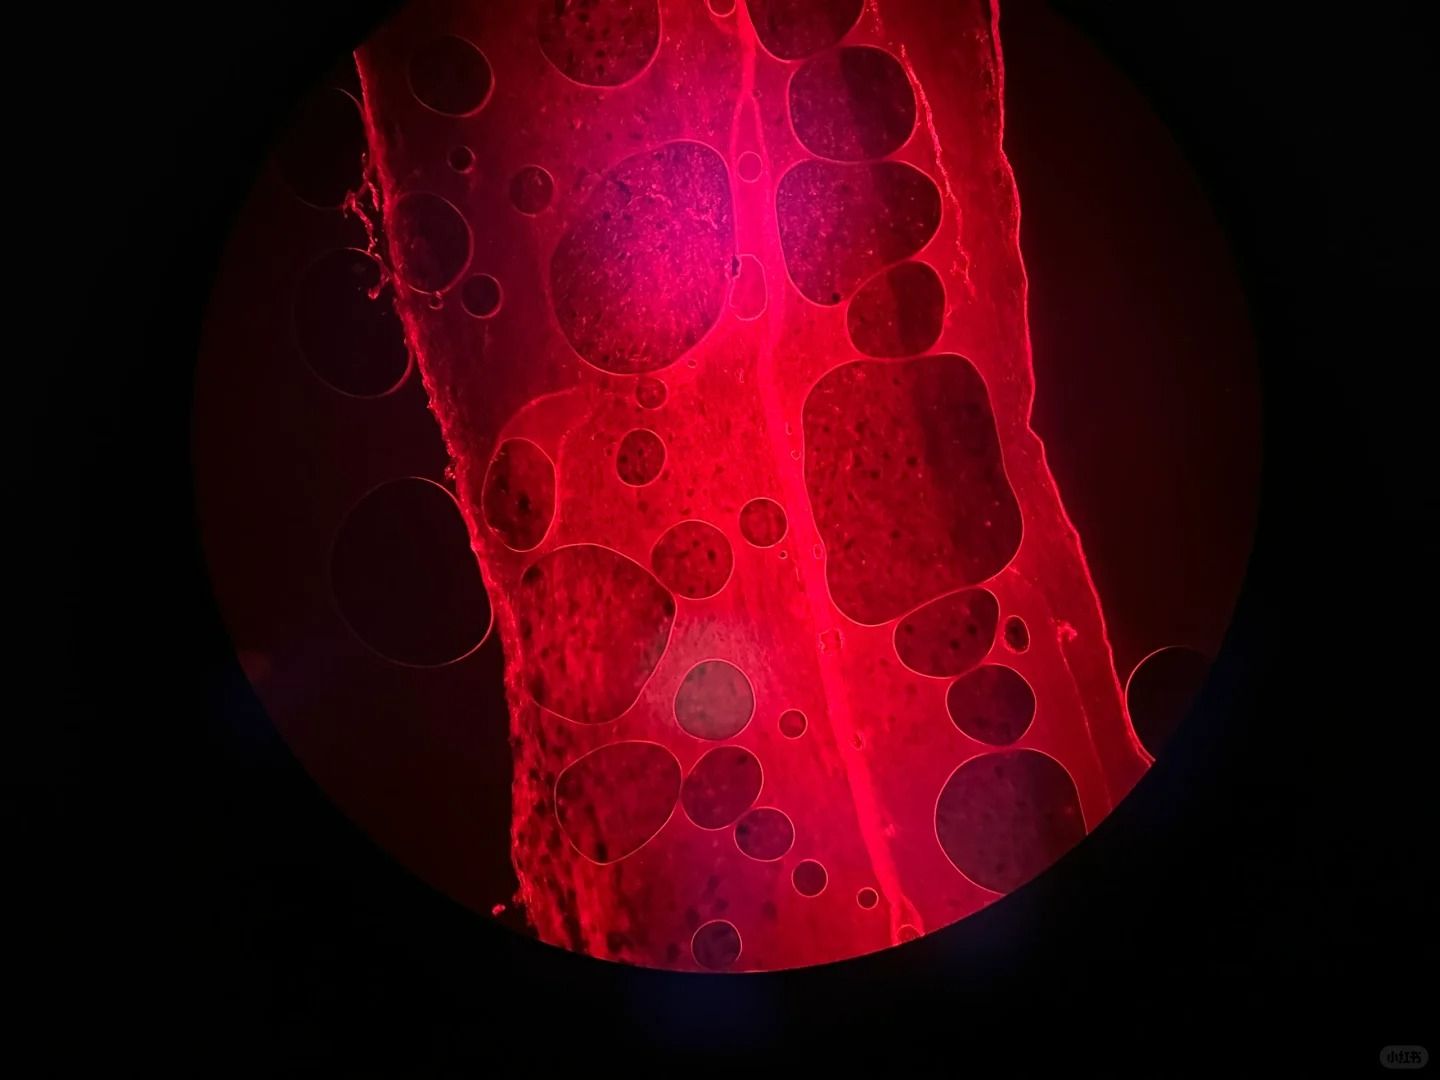

六、切片表面有氣泡

切片表面出現(xiàn)氣泡,可能是組織冷凍時(shí)內(nèi)部含有過多水分或空氣造成的。

為了消除氣泡,我們可以嘗試以下方法:

①在組織冷凍前,用吸水紙輕輕吸去組織表面的多余水分。

②在切片過程中,輕輕按壓切片,幫助排除氣泡。